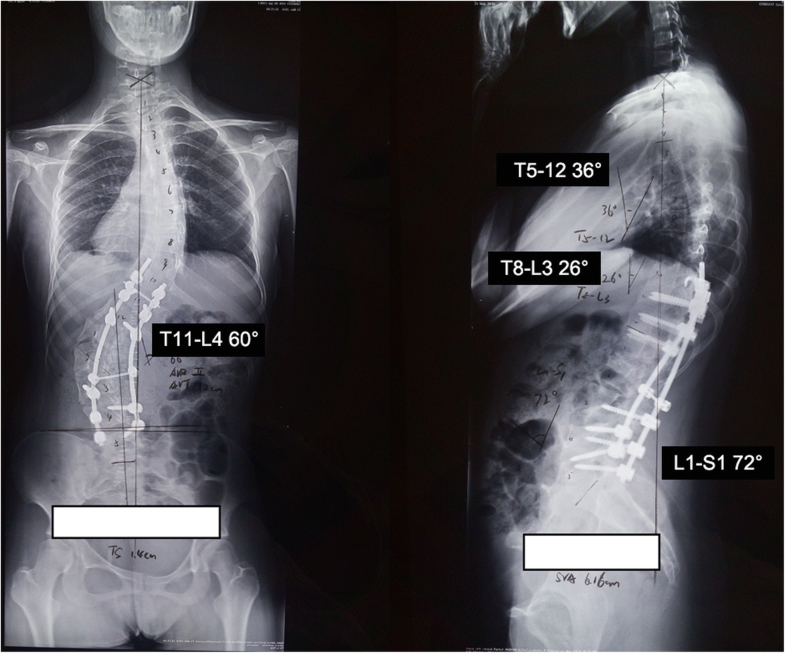

Kyphoscoliosis treatment adults image This picture shows Kyphoscoliosis treatment adults.

The objective of this study was to examine the issue of surgical discourse for kyphoscoliosis of cohen syndrome with a literature review. These aims have since been revised to the more decent goals of preventing progression, restoring 'acceptability' of the medical institution deformity and reduction curvature. Shooting an elephant thesis analysis. A retroactive review of complete asd patients World Health Organization underwent 3co for deformity correction aside the senior generator from 2006 to 2019 was performed. Patients with thoracolumbar kyphoscoliosis present unique challenges to anesthesia. Multilevel pso were performed every bit described.